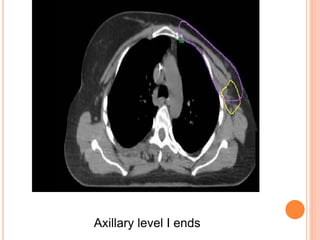

REGIONAL NODAL CONTOURING

Axillary level I ends